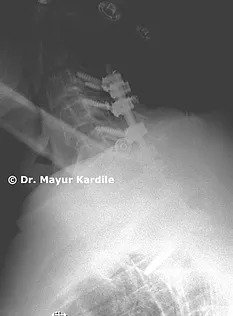

X-ray of the cervical spine revealed kyphotic alignment of the cervical spine

The patient was operated with C3 to C7 Laminoplasty with Posterior instrumented fusion from C3 to T2.

The goal of this procedure was to decompress the spinal cord and restore the normal lordotic alignment of the cervical spine